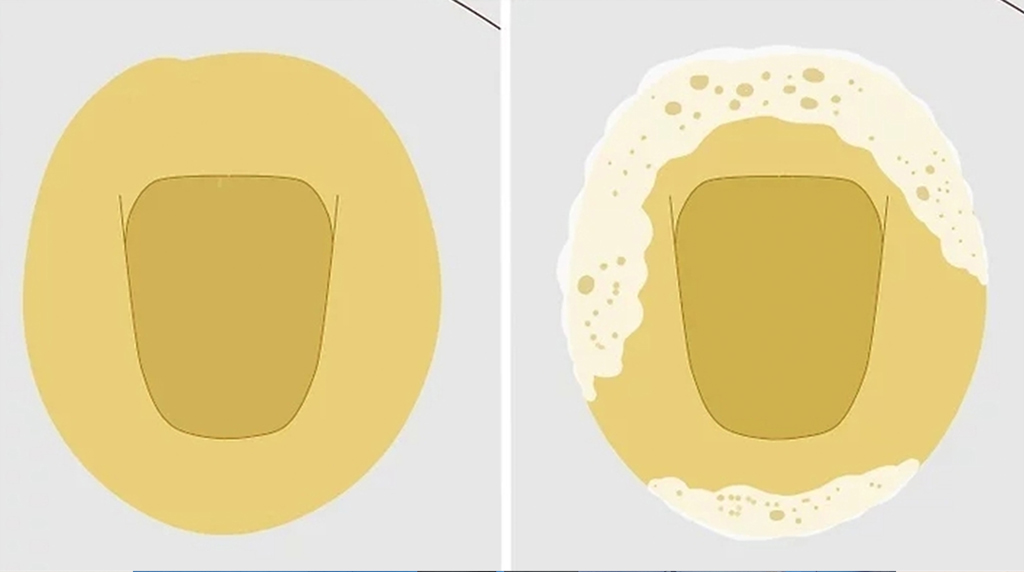

질환정보요단백 검사 수치 양성 원인 및 단백뇨 4가지 증상, 거품뇨

신장은 우리 몸에서 노폐물을 걸러내는 ‘정수기’와 같습니다. 이 정수기의 필터가 고장 나면 몸에